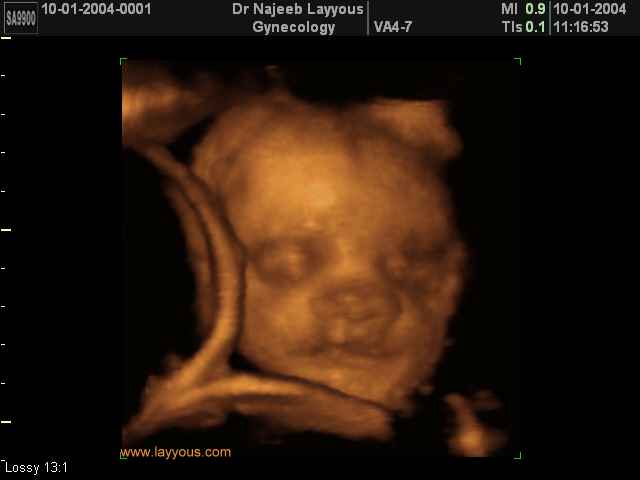

صور لوجه الجنين بجهاز الالتراساوند ثلاثي الأبعاد | الدكتور نجيب ليوس

صور لوجه الجنين بجهاز الموجات فوق صوتية ثلاثي الأبعاد